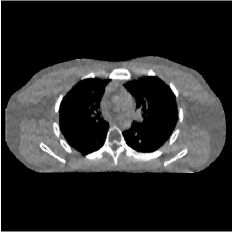

We pre-learned two transforms (Fig. 1) for the proposed two-layer model from image patches extracted from five XCAT phantom [24] slices, with , , and a patch extraction stride . We ran iterations of the learning algorithm in Section 3.1 to ensure convergence. We simulated 2D fan-beam CT test scans using XCAT phantom slices (air cropped) that differ from the training slices, with pixel size mm. Noisy sinograms of size were numerically simulated with GE LightSpeed fan-beam geometry corresponding to a monoenergetic source with , , and incident photons per ray and no scatter, respectively. We reconstructed two images with a coarser grid, where mm. The ROI here was a circular (around center) region containing all the phantom tissues.

Fig. 2 shows representative reconstructions for FBP, PWLS-EP, PWLS-ST, and PWLS-MRST2. Compared to FBP and PWLS-EP, PWLS-MRST2 significantly improves image quality by reducing noise and preserving structural details. Furthermore, PWLS-MRST2 improves the quality of the central region and image edges compared to PWLS-ST.

| (a) FBP | (b) PWLS-EP | (c) PWLS-ST | (d) PWLS-MRST2 |